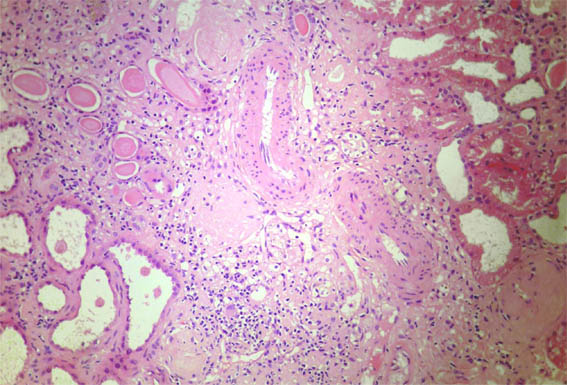

Figure 2. Masson's

trichrome stain X100.